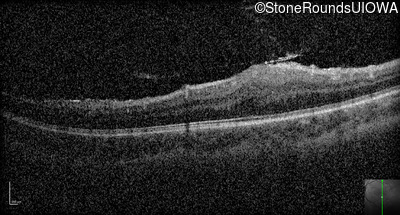

Optical Coherence Tomography - Right - 20/400

Exemplar